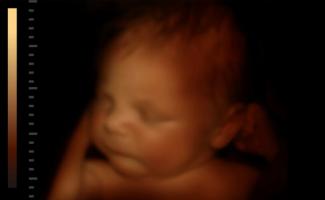

Nenarodené dieťa sa usmieva po tom, čo počas ultrazvuku počulo hlas otca